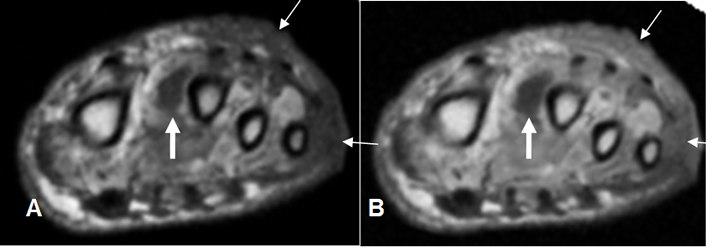

Fig 125 C. Pie diabético.

A: RM axial en T1 simple, B: RM axial en STIR y C: RM axial en T1 con contraste.

Pie diabético con cambios inflamatorios en los músculos plantares, hipointensos en T1 e hiperintensos en STIR. (Flechas delgadas). Con el contraste hay zona que no realza, sobre el 5º metatarsiano, por la presencia de tejido desvitalizado. (Flecha gruesa).